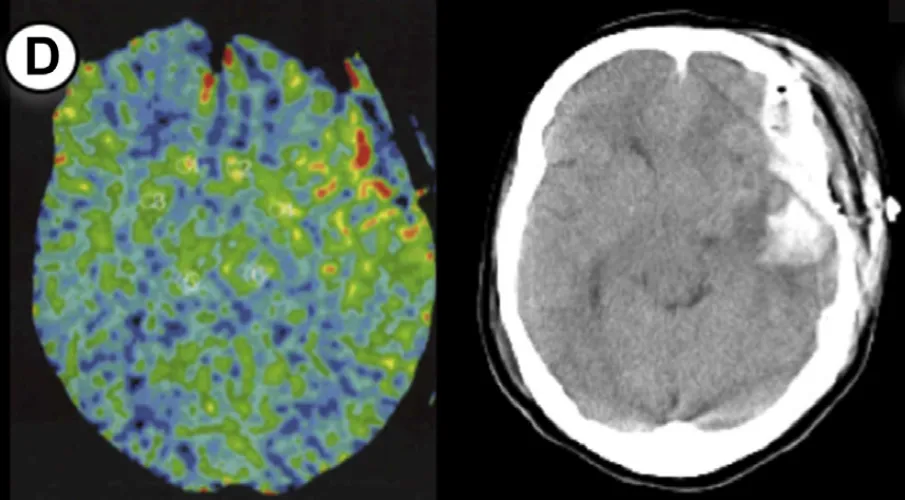

病例4

49岁女性,有TIA病史,行右侧大脑手术。方法1 rCBF增加率89%,方法2达133%。术后即时CT无异常,但第5天发现硬膜下血肿合并蛛网膜下腔出血。

7例病例年龄范围25-55岁,出血类型包括脑出血(ICH)、蛛网膜下腔出血(SAH)、硬膜下血肿(SDH)及混合出血,发病时间集中于术后1-5天。所有病例rCBF增加率均超过阈值,证实了预警系统的可靠性。

通过氙气增强CT,在大脑中动脉供血区固定部位测量rCBF,术后即时完成首次检测。